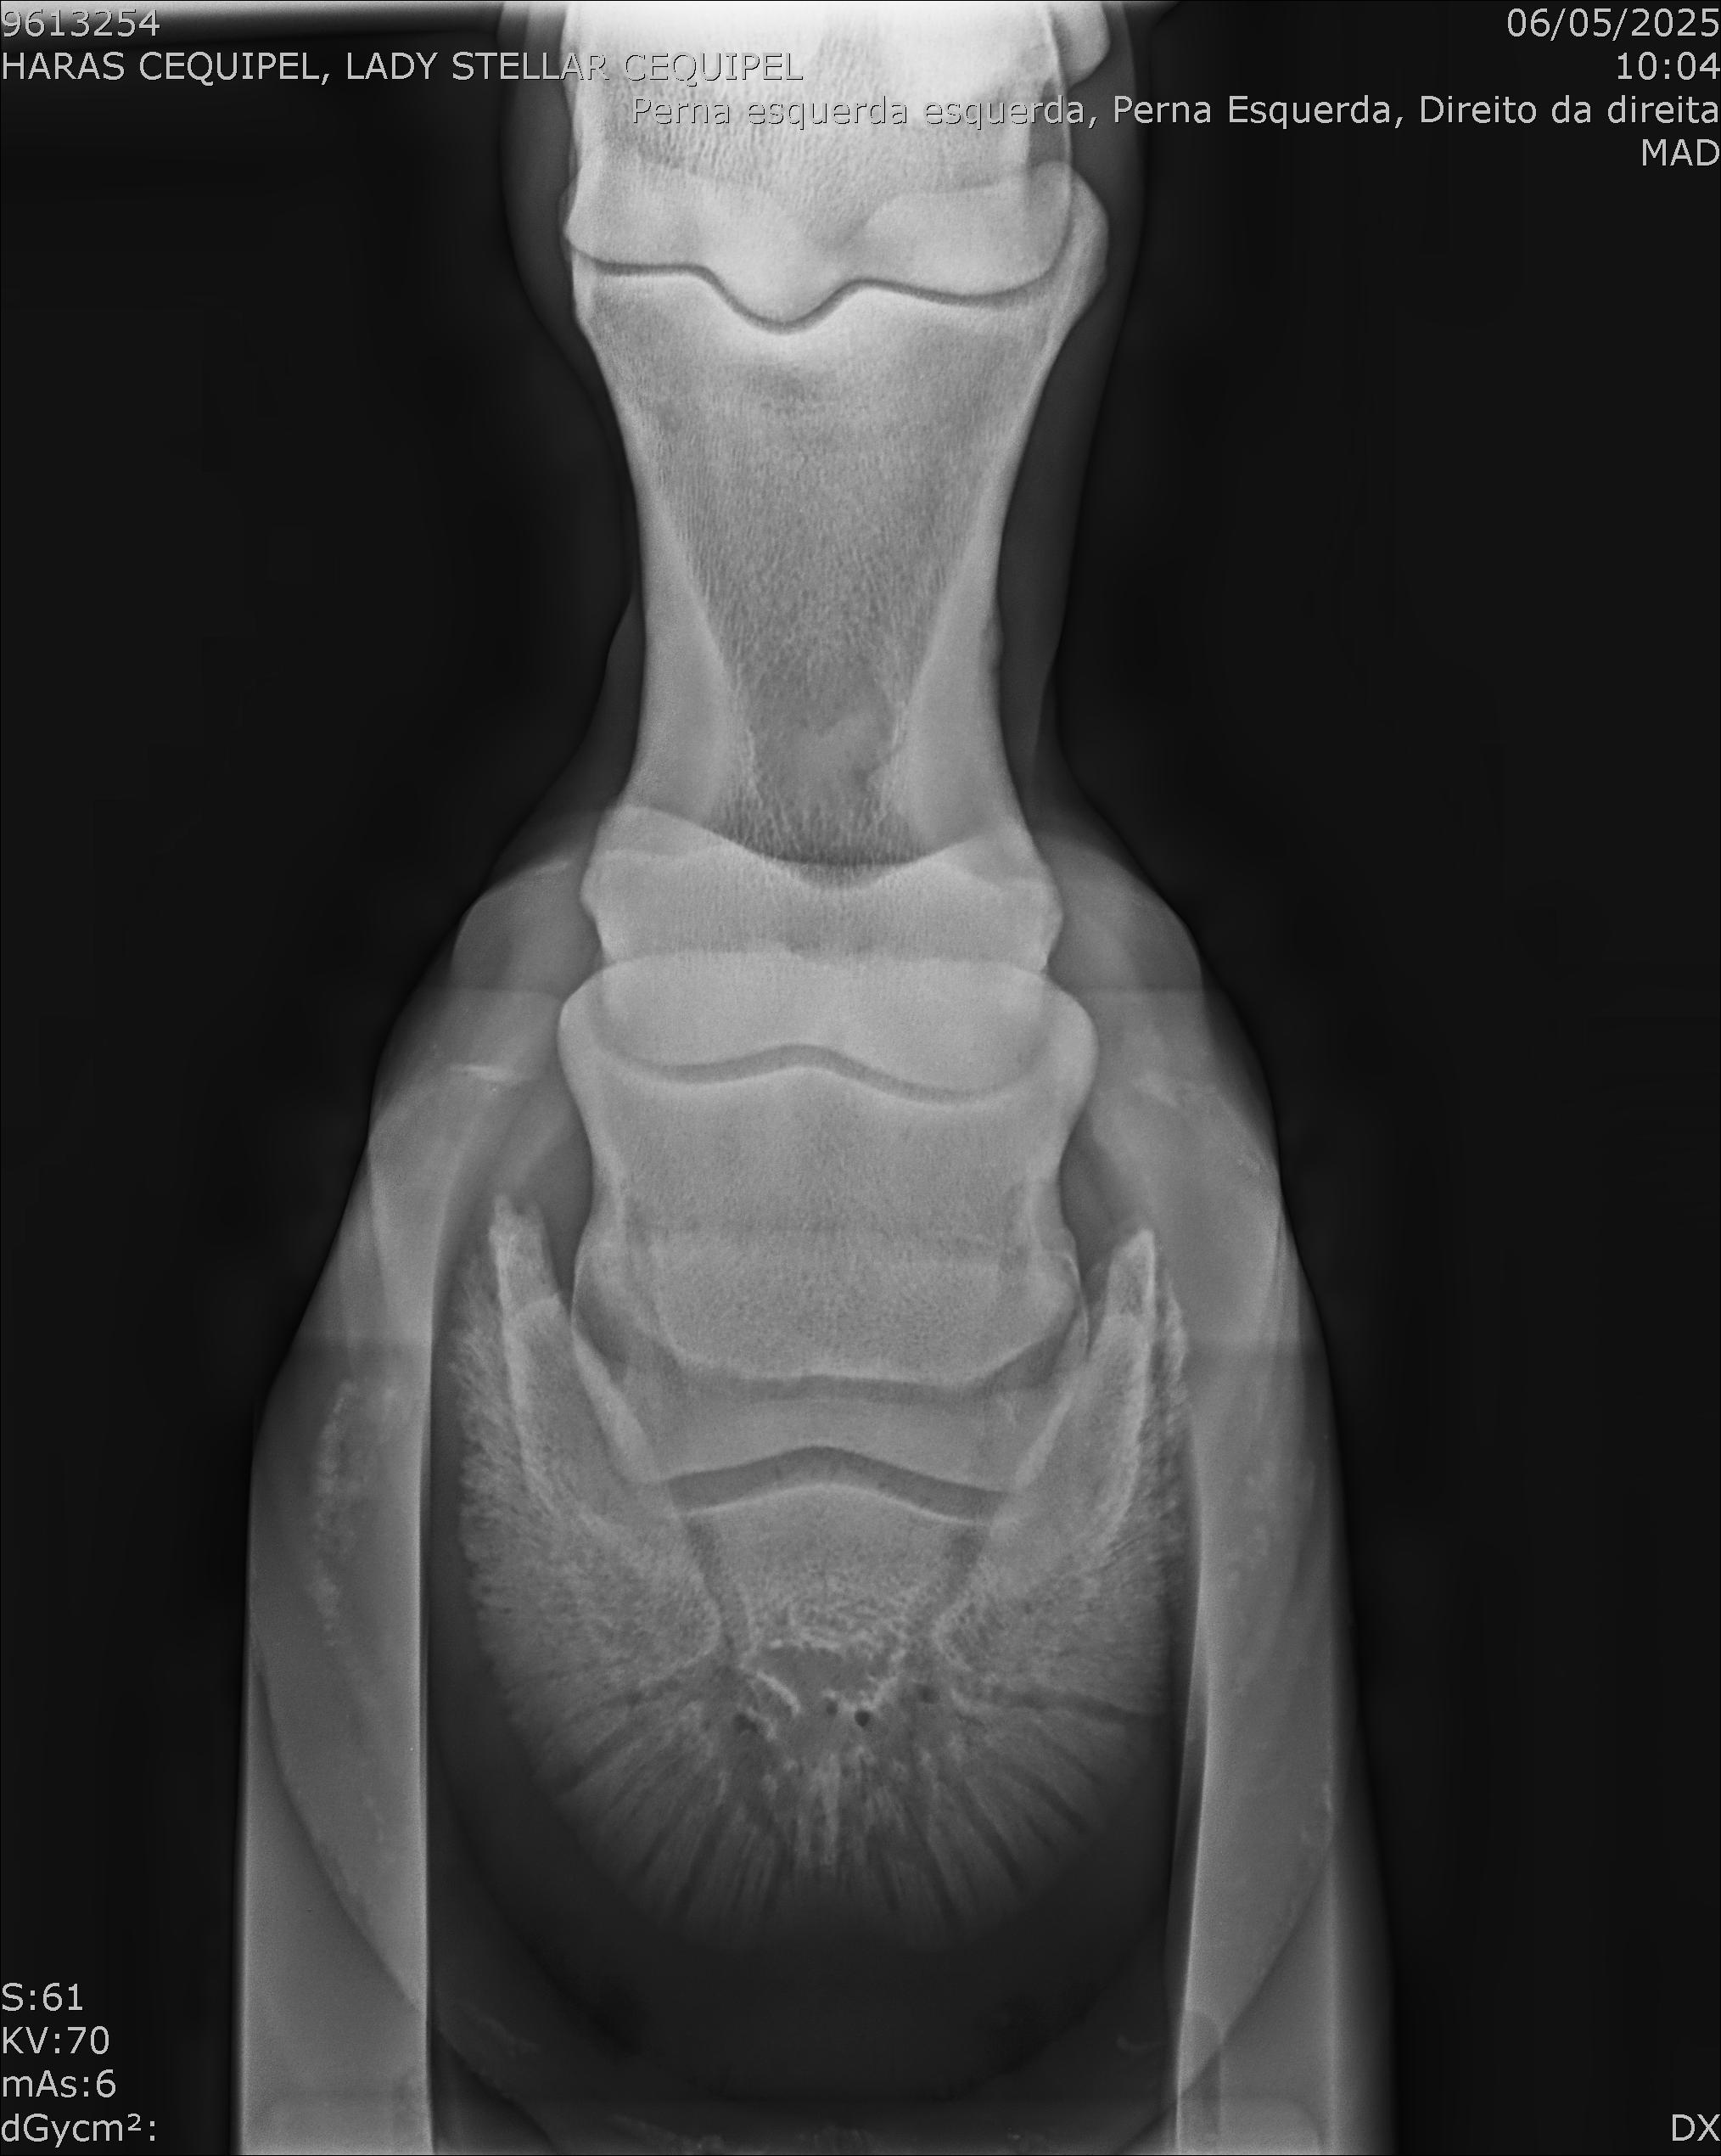

:: RAIOS-X DO LOTE